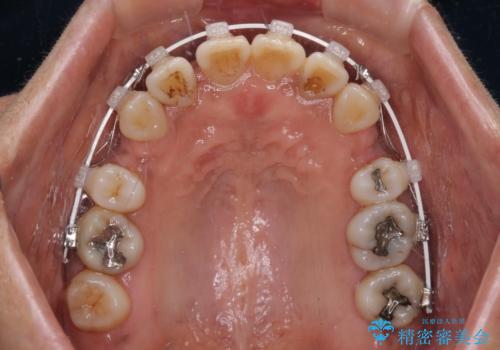

- 審美装置

- 2年4ヶ月

- 10-30回

口元の突出感はありませんでしたが、デコボコが強く、非抜歯矯正とすると出っ歯仕上がりとなる可能性があったため、上下左右の第一小臼歯4本を抜歯し、ワイヤー装置にて矯正治療を行うこととしました。